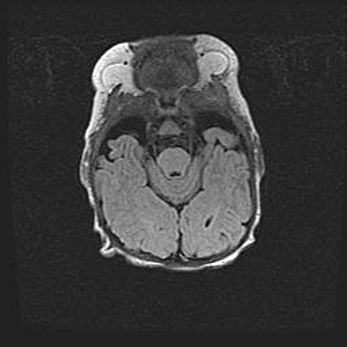

Открытая гидроцефалия.

Возраст: 9 месяцев 12 дней

Вес: 6800 г

Пол: мужской

Окружность головы: 41,5 см

Срок гестации: 28 недель

Гидроцефалия головного мозга у новорожденных имеет характерный признак: опережающий рост окружности головы приводит к визуально хорошо определяемой гидроцефальной форме сильно увеличенного в объёме черепа. Детские неврологи определяют следующие симптомы гидроцефалии у грудничков: выбухающий напряжённый родничок, частое запрокидывание головы, смещение глазных яблок к низу.